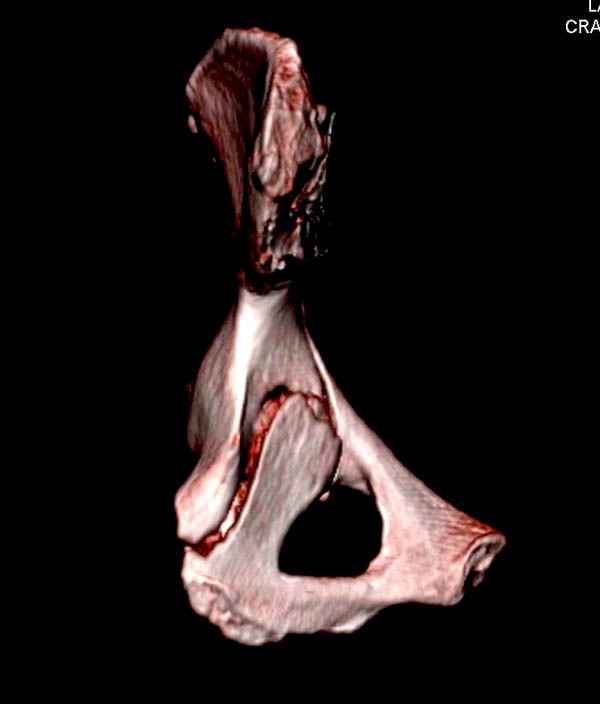

На снимке ацетабулума редко встречающийся очень низкий перелом,

наверное, трудно было репозицию через один доступ? Перелом как бы

замкнулся в квадрилатеральной поврехности.

Имя     : 12 acetabulum fem neck 3D.jpg

Тип     : image/jpeg

Размер  : 23128 байтов

Описание: отсутствует

Url     : http://weborto.net:8080/pipermail/ortho/attachments/20080116/651190cc/attachment-0012.jpg

Имя     : 14 acetabulum fem neck 3D.jpg

Размер  : 27750 байтов

Url     : http://weborto.net:8080/pipermail/ortho/attachments/20080116/651190cc/attachment-0013.jpg

Имя     : 15 acetabulum fem neck 3D.jpg

Размер  : 24795 байтов

Url     : http://weborto.net:8080/pipermail/ortho/attachments/20080116/651190cc/attachment-0014.jpg